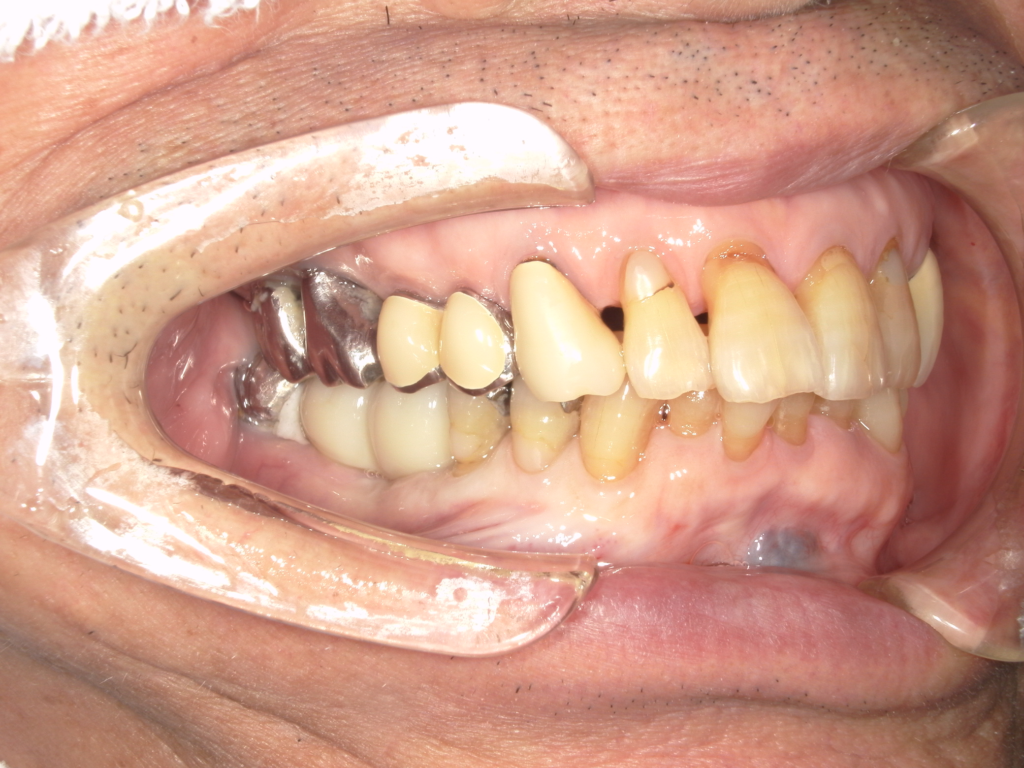

Y様インプラント実例 #44

左の上下の奥歯をインプラントで治療しています。

左下の奥歯は歯を抜くのと同時にインプラントの埋め込みを行っています。

被せものは上下、セラミックスで作っています。

治療前

治療後